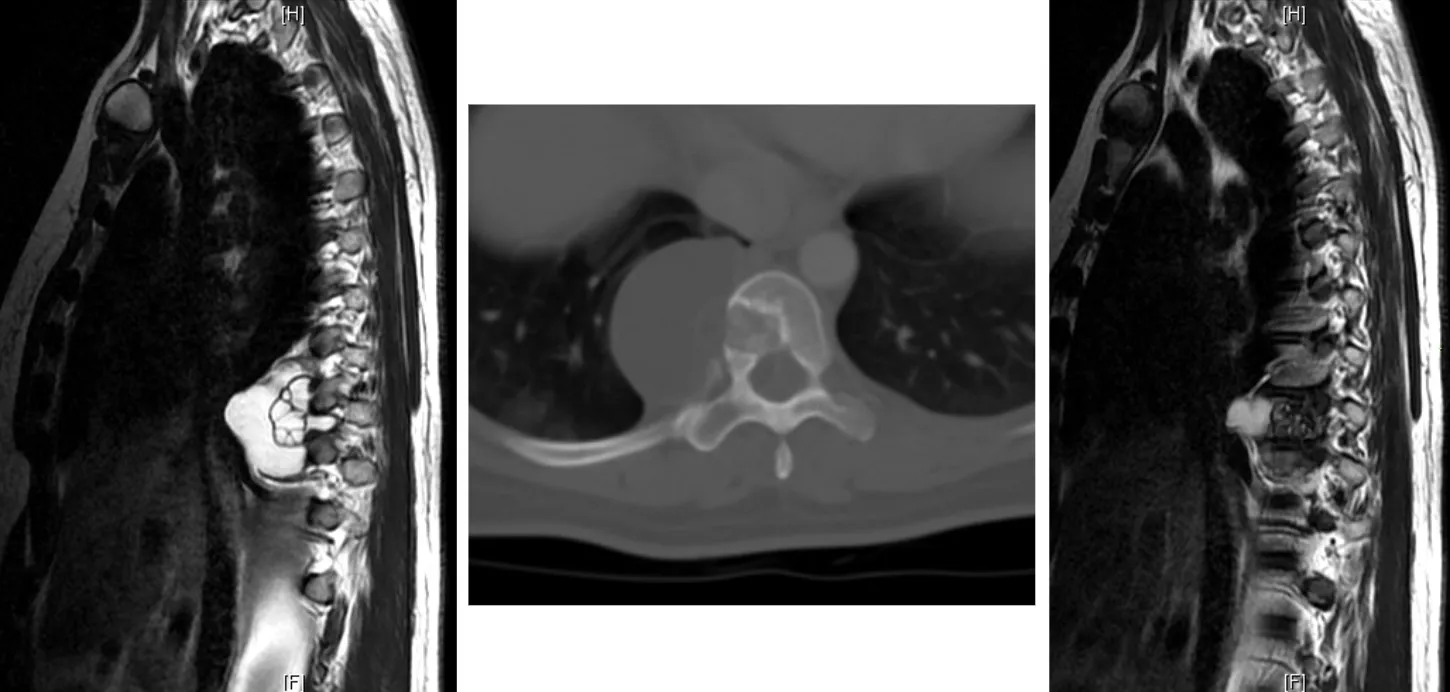

Resonancia magnética (RM)

Constituye la prueba de imagen de elección para el diagnóstico y seguimiento de la espondilodiscitis. La RM presenta una sensibilidad y especificidad superior al 90%, permitiendo una visualización óptima del disco, los cuerpos vertebrales, los abscesos epidurales y la afectación de partes blandas paravertebrales.

La clasificación de la espondilodiscitis por resonancia magnética distingue diferentes estadios según los hallazgos radiológicos:

| Estadio | Hallazgos |

|---|---|

| Estadio I | Hematoma y radiolucidez localizada en los platillos de la vértebra |

| Estadio II | Edema vertebral y/o sospecha de acumulación de líquido dentro del cuerpo vertebral con mala demarcación de la lesión |

| Estadio III | Intensidad de señal irregularmente aumentada en la resonancia con confinamiento dentro del ligamento longitudinal posterior |

| Estadio IV | Acumulación evidente de líquido en el disco asociado a destrucción de los platillos y extensión a lesiones epidurales |

| Estadio V | Desaparición del disco con colapso vertebral y afectación del cuerpo vertebral y arco posterior así como de los ligamentos y músculos paravertebrales |